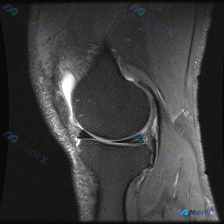

刚整理了一份很有启发的膝关节MRI读片病例,分享给大家,尤其能帮我们避避临床思维的坑。 病例核心影像信息 这是一例膝关节MRI T2序列矢状位影像,送检原因是怀疑存在半月板异常,系统评估各结构如下: 1. 骨骼关节软骨:股骨远端、胫骨近端、髌骨轮廓正常,股骨滑车和胫骨平台关节软骨大致平滑,无明显全层...

给大家分享一个很有启发的膝关节MRI读片病例,临床关注点是半月板异常,读完片发现其实核心问题不在这儿,整理一下完整分析思路。 病例影像基本信息 这是一份膝关节矢状位T2加权MRI(压脂序列),我们先整理所有客观发现: 1. 关节内结构:半月板形态完整,呈典型低信号三角表现,未见贯穿性高信号,边缘光滑...

看到一份很有启发的膝关节MRI病例,初始提示是「半月板异常」,但读片后的发现和一开始的方向完全不一样,整理一下完整分析思路跟大家分享。 一、病例影像基础信息 这是膝关节MRI矢状位T2加权图像,我们先整理所有客观发现: 1. 骨骼关节:股骨远端、胫骨近端、髌骨骨皮质完整,无明显骨折或骨质破坏,髌骨与...

病例读片分享:临床怀疑半月板异常,MRI却只看到髌周病变 基本影像信息 提供的影像为膝盖MRI-T2序列矢状位,切面位于膝关节前部髌股关节区域,图像存在一定截断伪影,未显示后交叉韧带及大部分后侧软组织结构。 影像核心发现 整理一下客观观察到的异常: 1. 髌前皮下软组织水肿:髌骨前方及皮下组织层可见...

看到这份有意思的病例,主诉是提示半月板异常的膝关节MRI,整理了完整的读片思路和分析,分享给大家。 一、影像基础信息 这是一幅膝关节MRI T2加权矢状位图像,我们先确认基础信息: - 成像序列符合T2WI特征:液体高信号、软骨中等信号、脂肪低信号、骨皮质及韧带低信号 - 切面展示膝关节前部结构:髌...